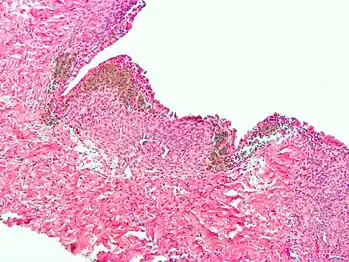

Histopathology

For a histopathological diagnosis, at least two of the following three criteria should be present:[126]

- Endometrial type stroma

- Endometrial epithelium with glands

- Evidence of chronic hemorrhage, mainly hemosiderin deposits

Immunohistochemistry has been found to be useful in diagnosing endometriosis as stromal cells have a peculiar surface antigen, CD10, thus allowing the pathologist go straight to a staining area and confirm the presence of stromal cells and sometimes glandular tissue is identified that was missed on routine H&E staining.[127]

Micrograph showing endometriosis (right) and ovarian stroma (left)

Micrograph of the wall of an endometrioma. All features of endometriosis are present (endometrial glands, endometrial stroma and hemosiderin-laden macrophages).